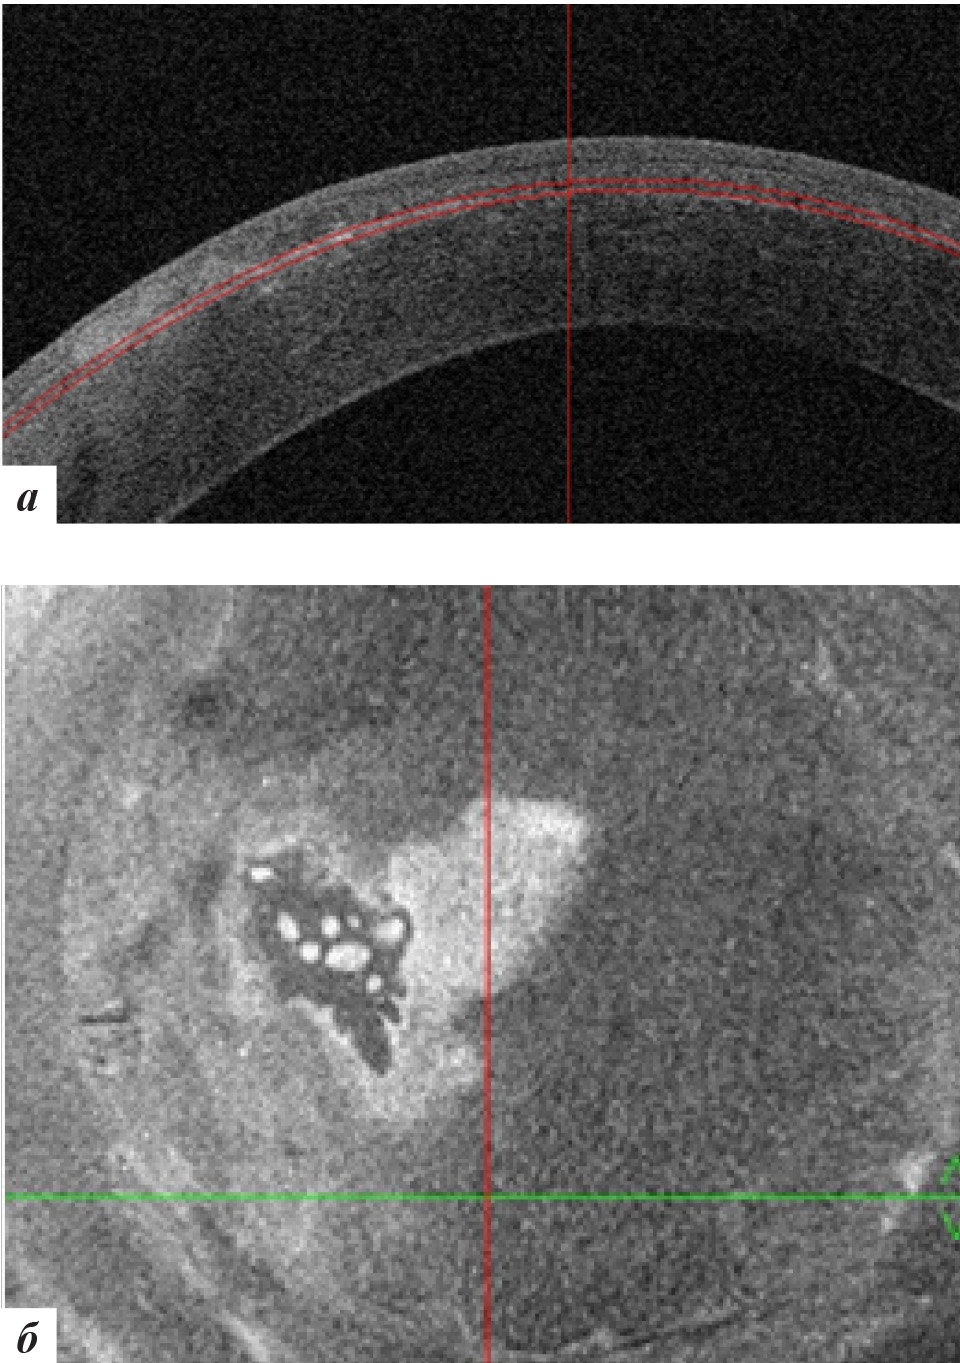

При офтальмобиомикроскопии OS в роговичном интерфейсе в центральной оптической и параоптической зонах отмечалось стойкое облаковидное помутнение при отсутствии рецидива роста эпителиальных клеток (рис. 10), подтвержденное данными ОКТ роговицы (рис. 11).

Рис. 11. Данные ОКТ роговицы левого глаза через 18 месяцев после лечения: а – горизонтальная проекция, б – фронтальная проекция